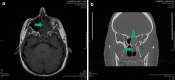

A 42 year old male presents with worsening pain and an increase in thick chronic drainage of the left sinus. Image studies show complete opacification of the left frontal sinus, left sphenoid sinus, and the left maxillary sinus. The patient was taken to the operating room and tissue for microscopic evaluation was obtained. The microscopic findings were classic for allergic fungal sinusitis: areas of alternating mucinous material and inflammatory cell debris and abundant Charcot-Leyden crystals. Cultures were performed and the patient began steroid therapy and desensitization therapy.